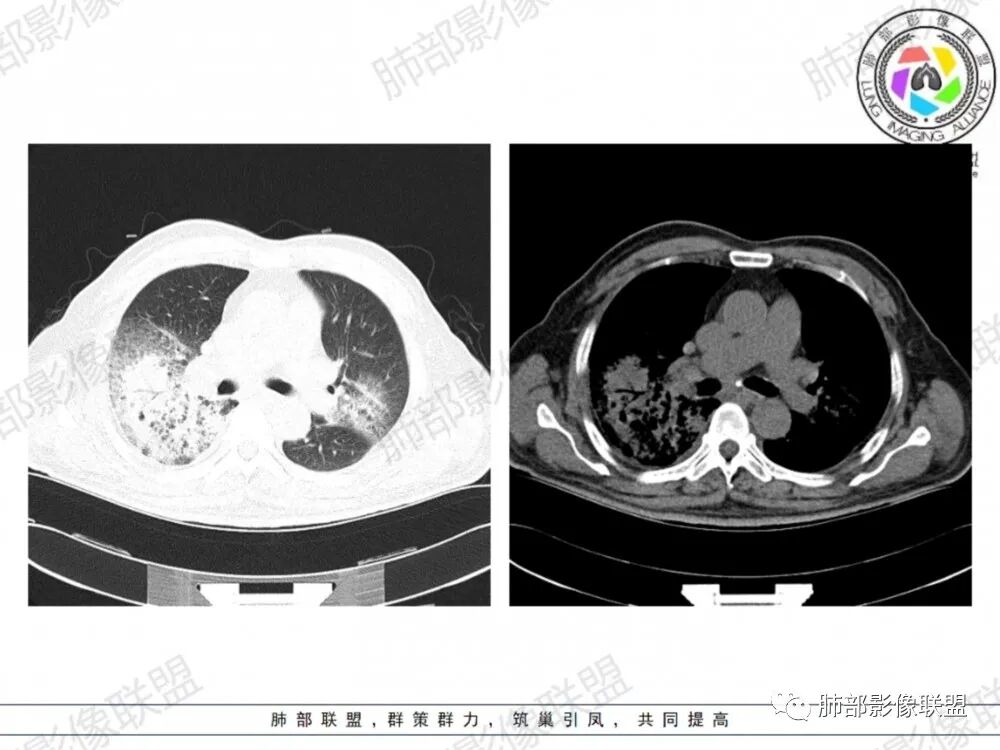

晨读:老年男性患者,咳嗽气喘3天入院,伴有发热,体温38.2℃,有糖尿病,高血压病史,有长期吸烟史,近期旅游史,白细胞,中性粒,CRP,PCT增高,肝功能损害,血气分析:低氧血症,胸部CT:双上肺及右下肺实变密度影伴周围磨玻璃密度影,边界整体清楚,内部支气管走形自然,伴双侧少量胸腔积液,综合考虑感染性病变,重症社区获得性肺炎,重点考虑非典型病原体,军团菌可能,鉴别肺克,结核合并感染

晨读老年患者,咳嗽气喘三天,腹泻,有多脏器的损害。有基础病的病史,糖尿病,高血压。旅游病史。两位靠后分布的大片状的实变影及磨玻璃样阴影,跨叶小叶性的分布,支气管充气征。内部的小叶间隔局部增厚。纵隔淋巴结不大,右侧胸腔积液。首先考虑感染性的病变,靠后重力感,肺克雷伯杆菌肺炎。鉴别诊断军团菌肺炎。

双肺多发斑片及大片状高密度影,周围伴磨玻璃影,界欠清晰,内见多发囊状透亮影呈蜂窝状,病变内支气管走形规则,无肺气肿背景,双侧胸腔积液,老年男性,糖尿病史,消化道症状,炎性指标升高,考虑军团菌感染,克雷白杆菌感染待排。

双肺大片磨玻璃影伴实变,边缘清晰,支气管通畅,磨玻璃影部分呈细网格状,胸膜下清晰,双侧胸腔积液,心影增大,心腔密度减低,贫血,考虑肺克,军团菌

胸部CT示双肺弥漫实变影伴周围磨玻璃影,跨叶段分布,可见小叶间隔增厚,支气管充气征,双侧胸腔积液。无明显坏死空洞及树芽征。

CT:双肺多叶段毛玻璃影、实变影、小叶内间质增粗,肺内病变有重力依赖趋势,双侧少量胸腔积液,无空洞、树丫;

网格影还是比较明显,反晕征的壁在胸膜上,总体感觉病灶比较牢固,被钉紧的感觉,还是军团菌多见一些。

军团菌感染可累及多个脏器,肺是主要的受侵器官。军团菌肺炎为广泛多叶分布的炎症。

1.病变复杂多样∶大片状实变影、斑片状模糊阴性,网格状阴性、小结节影。多叶受侵是本病重要影像学特征性改变。

3.呈小叶肺炎状改变,病变大小以肺小叶为单位的支气管肺炎,呈弥漫性的单或双侧分布。局部可融合呈高密度的团片状影像,本病又一典型的影像学特点。

4.病变常伴有胸水出现,肺部阴性多变的情况下伴有胸水形成应高度怀疑军团菌感染的可能。